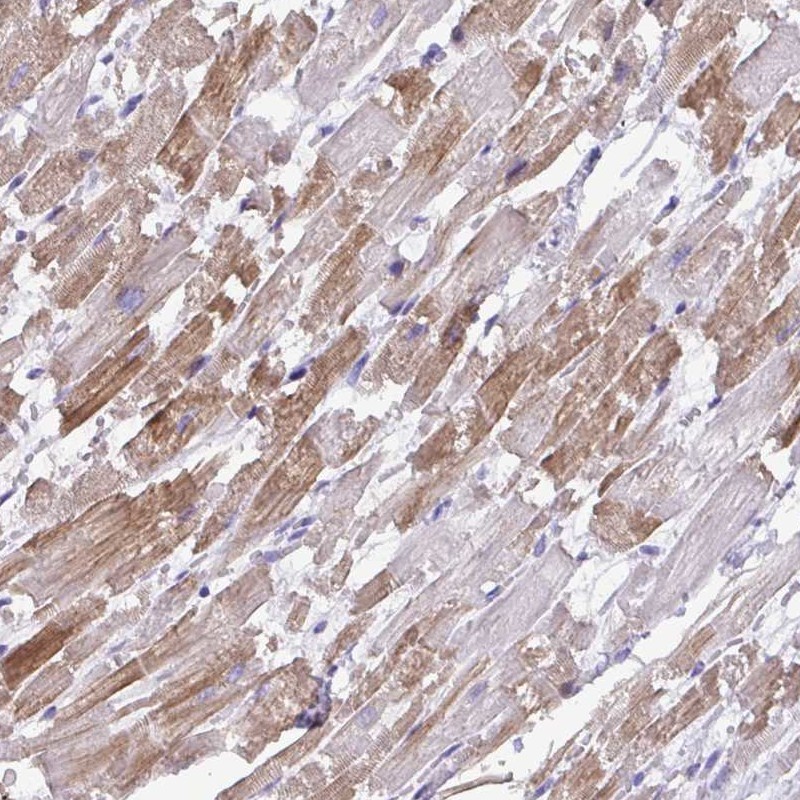

Immunohistochemical staining of human heart muscle shows cytoplsmic positivity in myocytes.